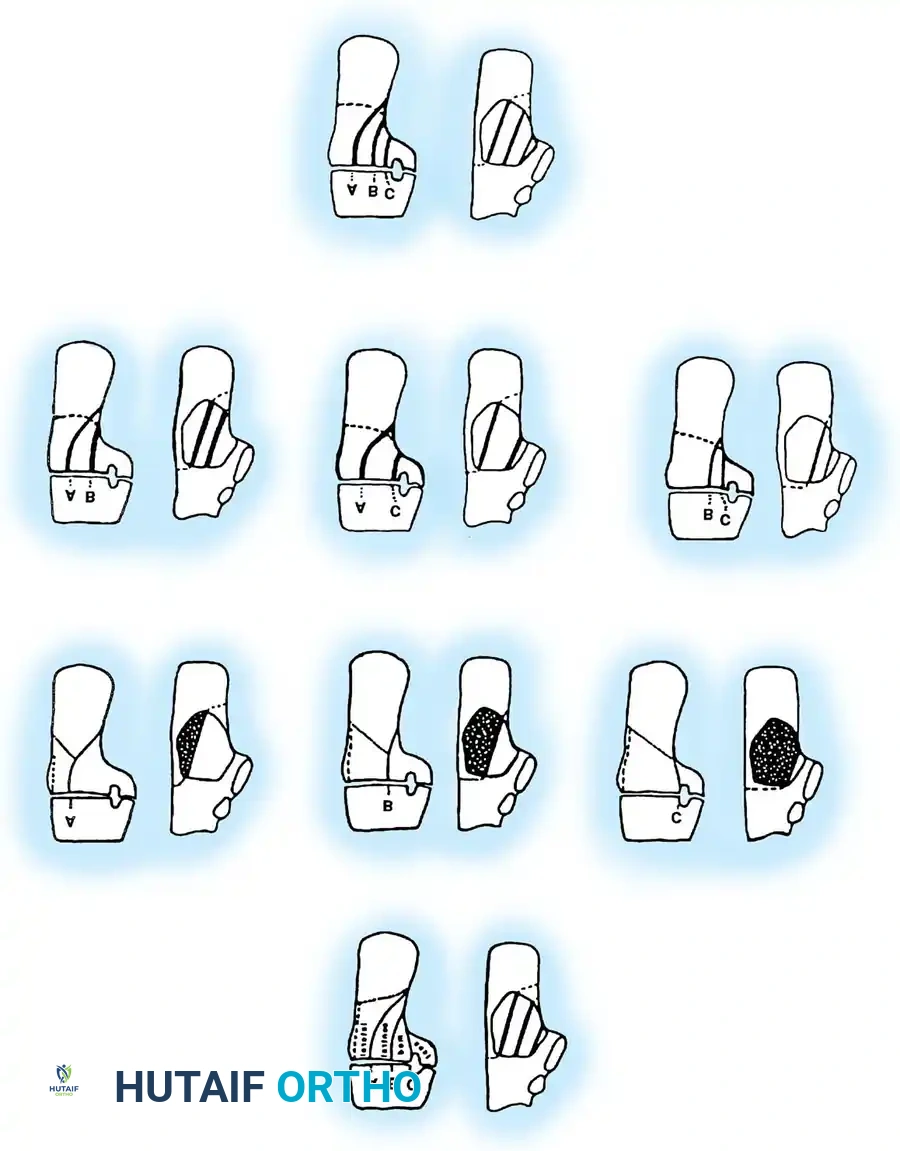

The Sanders Classification

The Sanders classification has become the universally accepted system for intraarticular calcaneal fractures. It is based on the number and location of articular fracture lines seen on the semicoronal CT image showing the widest portion of the posterior facet.

The posterior facet is divided into three potential fracture lines (A, B, and C), creating four potential fragments (lateral, central, medial, and sustentacular).

* Type I: All nondisplaced fractures (regardless of the number of fracture lines).

* Type II: Two-part fractures of the posterior facet (one fracture line). Subdivided into IIA, IIB, or IIC based on the location of the line.

* Type III: Three-part fractures (two fracture lines), featuring a centrally depressed fragment. Subdivided into IIIAB, IIIAC, or IIIBC.

* Type IV: Four-part (or more) highly comminuted fractures.

Clinical Pearl: Ebraheim et al. demonstrated that CT scans may occasionally underestimate the sagittal plane rotation of a depressed fragment. Therefore, plain lateral radiographs must always be correlated with CT findings to fully appreciate the three-dimensional deformity.